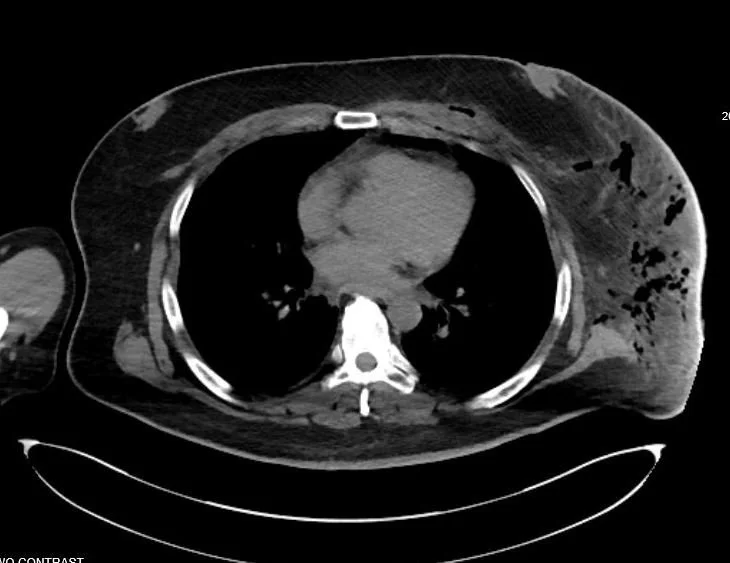

CT scan of our patient showing gas in the tissue.